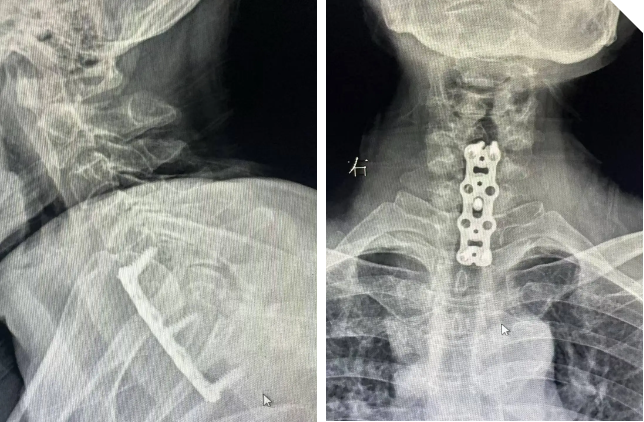

术后影像片

在饶放萍主任医师的带领下,手术团队配合娴熟,凭借丰富的临床经验与精湛的手术技艺,精准定位病灶位置,彻底清除病灶组织,同时进行椎管减压,充分解除脊髓压迫。为确保颈椎的稳定性,还从患者自身髂骨取骨,进行结构植骨并实施内固定。整个手术过程紧张有序,通过专家团队近2小时的“精雕细琢”,终于大获全胜!

术后,在医护团队的精心护理与康复指导下,李阿姨的恢复情况超出预期。术后不久,她的四肢肌力便有了明显改善,之前存在的疼痛、麻木等症状逐渐缓解。颈椎化脓性感染快速得到控制、脊髓神经功能持续恢复。术后2周出院时,李阿姨已能够佩戴颈托支具下床活动,生活基本可以自理。